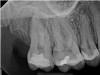

The second case study is that of a healthy 88-year-old woman who presented with significant bone loss on the mesial and apical aspect of tooth No. 18, which would suggest potentially a vertical fracture in the tooth (Figure 9 and Figure 10). The clinician had initially recommended extraction, which they informed the patient would likely be the best course of action, especially given that she had plenty of bone anterior to the tooth to place implants. When the recommendation of extraction was made to the referring dentist, he had some resistance because both he and the patient were interested in saving the tooth. Although the clinician initially stood firm on the recommendation, he received a call from the general dentist about a month later. He further expressed their desire to save the tooth, and he asked if the endodontist thought the new technology, the GentleWave Procedure, could be a solution. The informed consent was obtained and the patient was scheduled for treatment. Because the canal was quite calcified apically, a defined working length could not be determined. Obturation was performed using warm vertical condensation of gutta-percha.

Fig 9. Case 2: Significant bone loss on the mesial and apical aspect suggested a potential vertical fracture (Fig 9 and Fig 10). Radiographic images were taken immediately postoperatively (Fig 11) and 7 months postoperatively (Fig 12).

Fig 10. Case 2: Significant bone loss on the mesial and apical aspect suggested a potential vertical fracture (Fig 9 and Fig 10). Radiographic images were taken immediately postoperatively (Fig 11) and 7 months postoperatively (Fig 12).